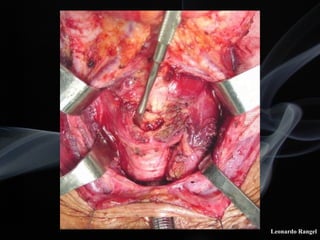

!TÉCNICA

LPSC